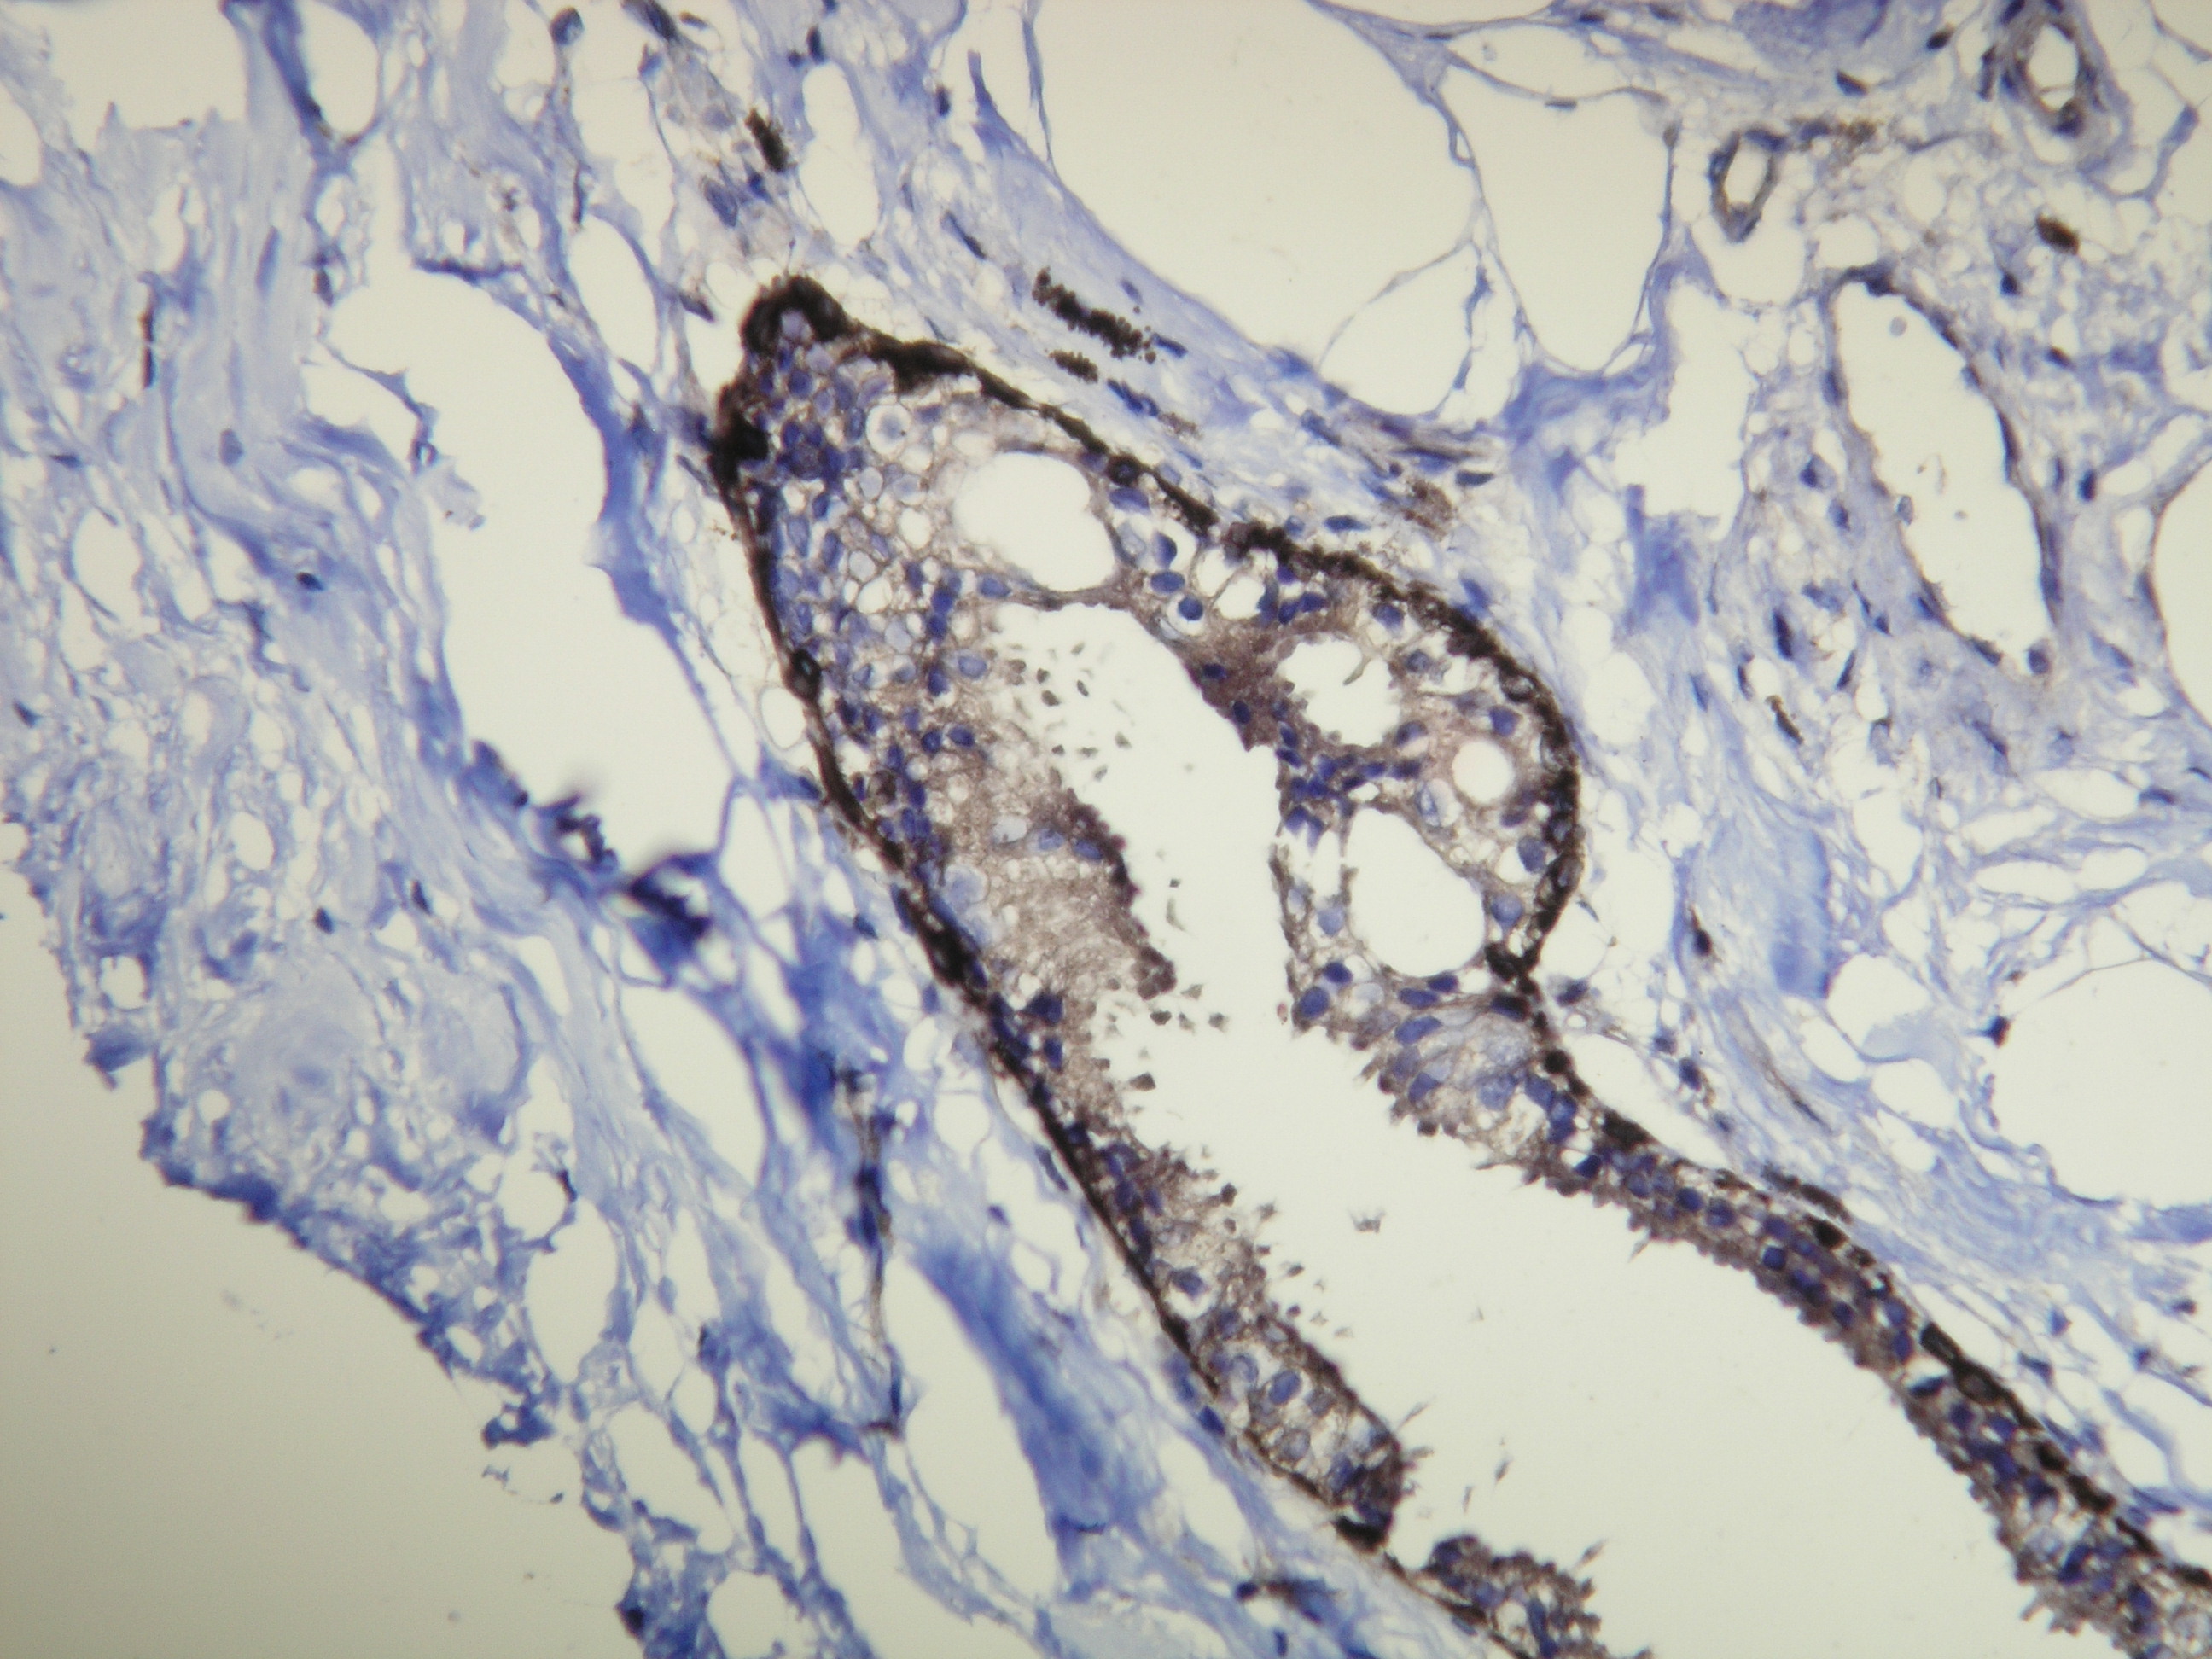

Anti-Cytokeratin 14

Peptid derivovaný z C-konca ľudského Cytokeratín 14 proteínu. Protilátka rozpoznáva epitop umiestnený medzi Val455 - Lys471.

IHC-P, riedenie 1:100

db099a db099b db099c